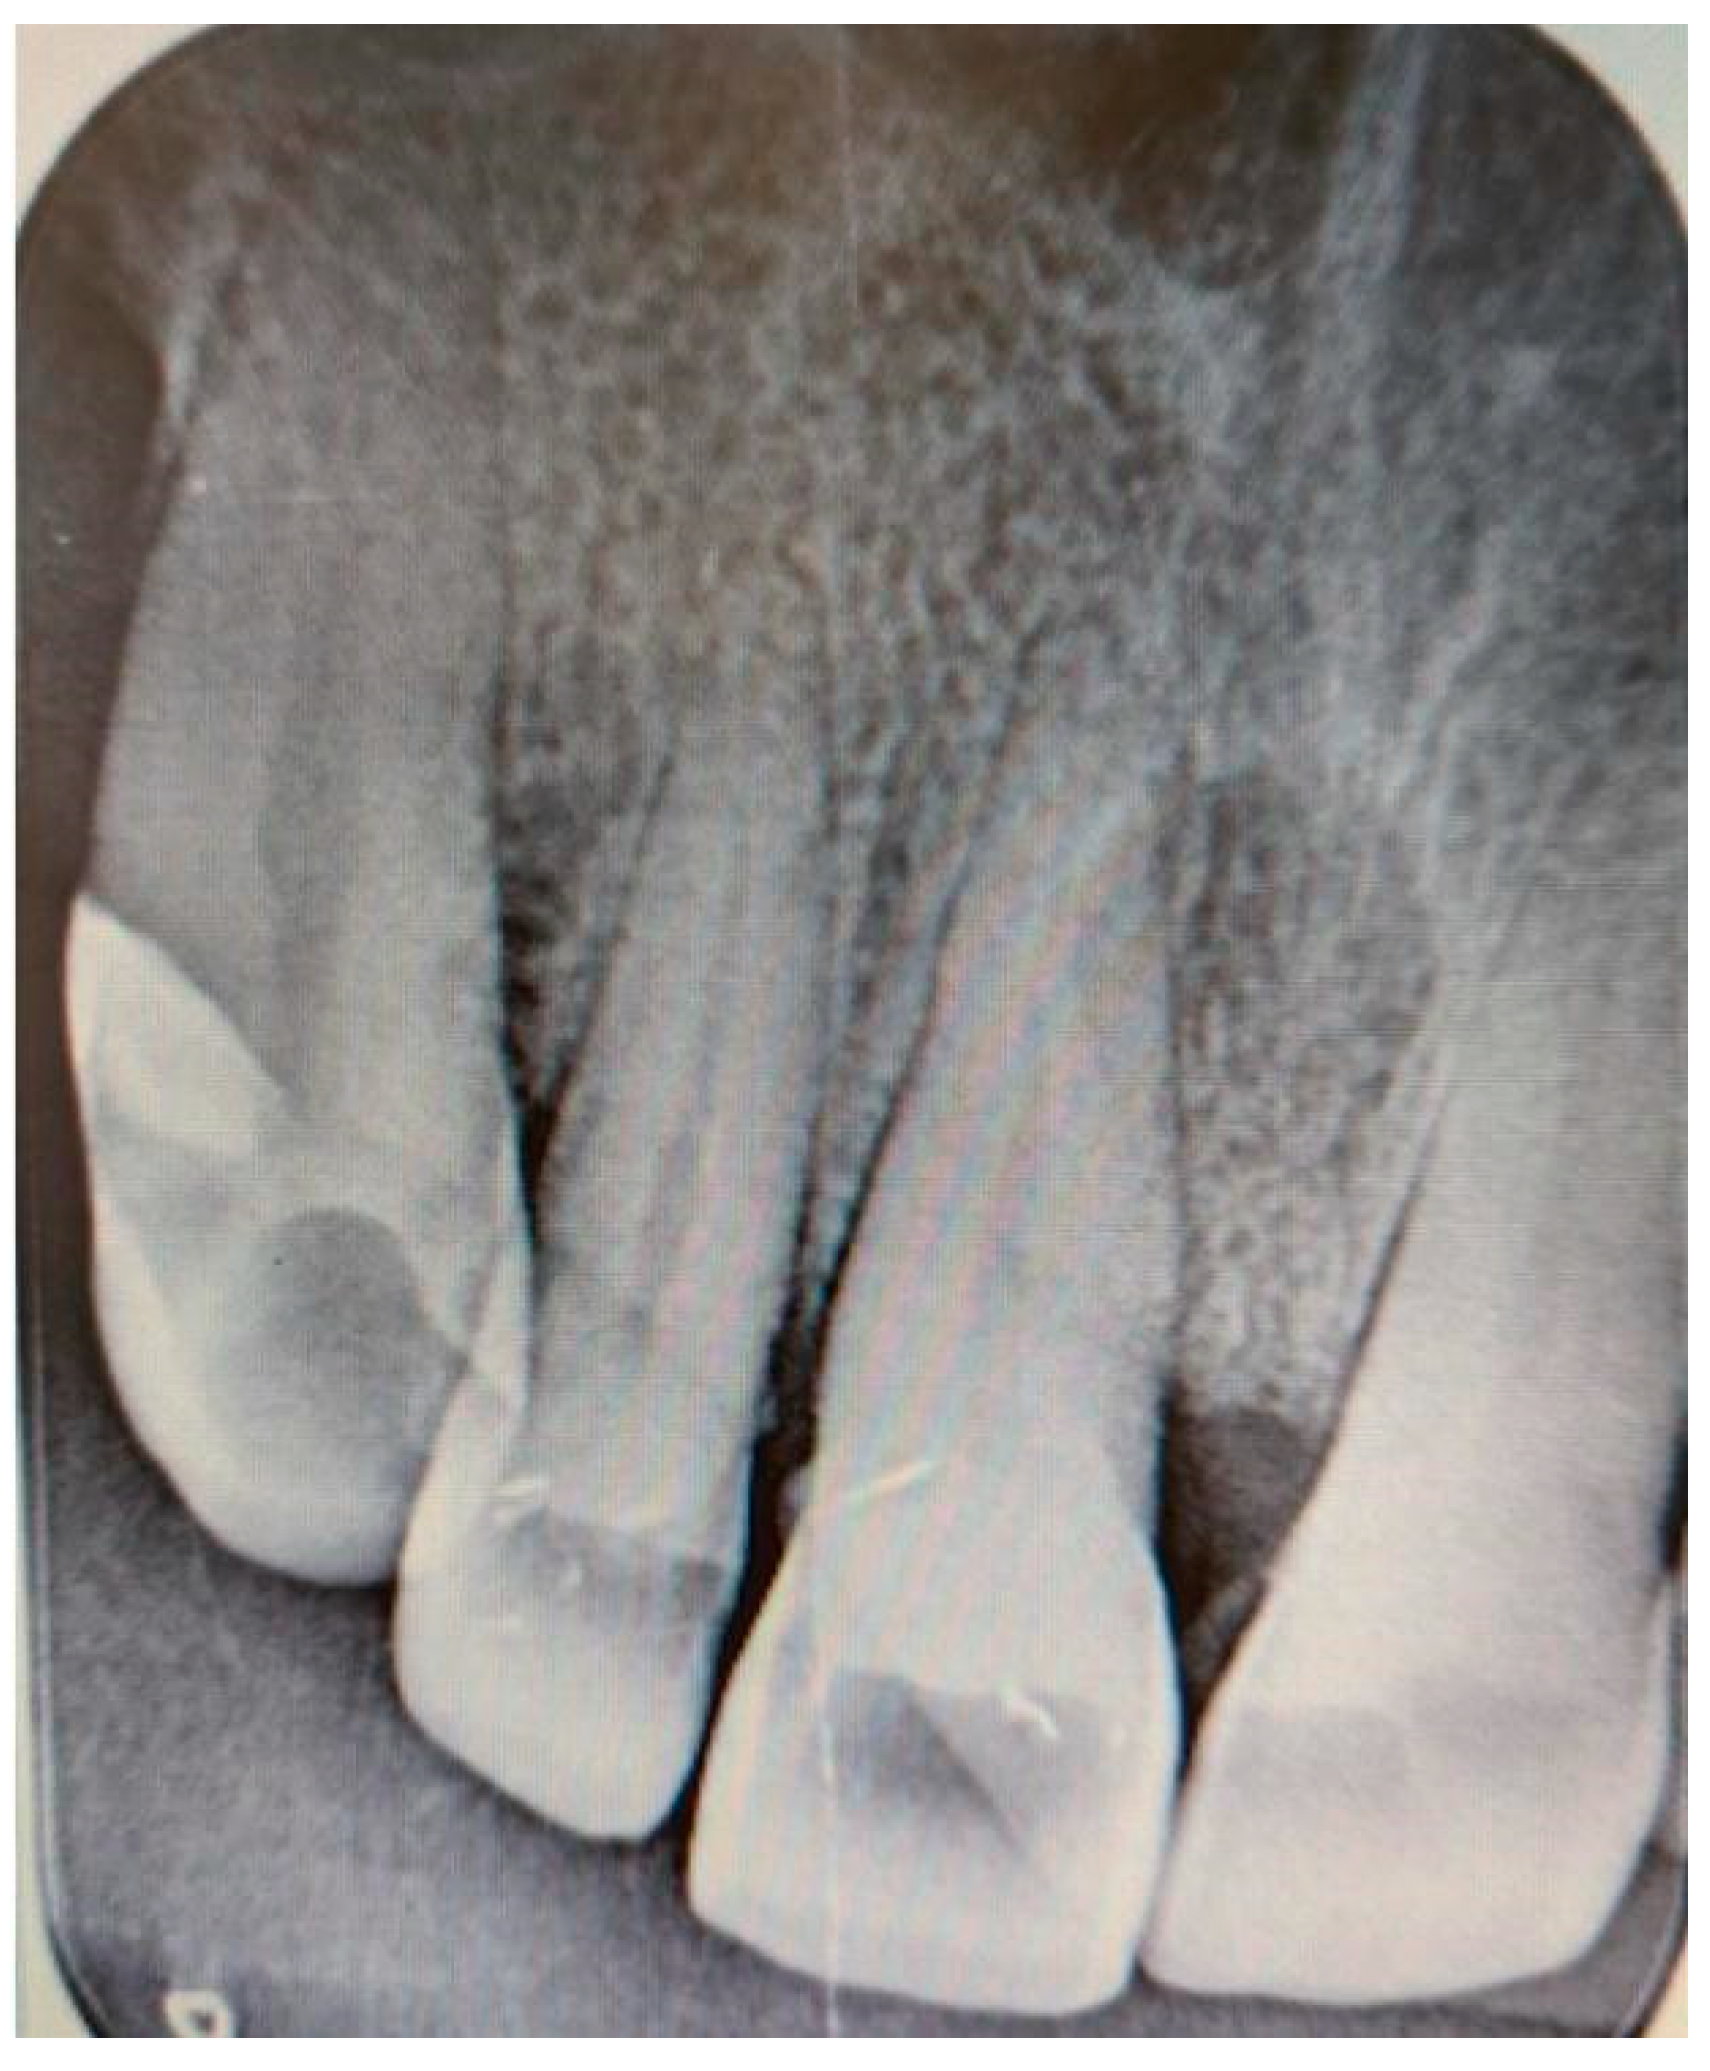

Additionally, digital periapical radiographs of the patient’s maxillary and mandibular incisors were taken to exclude periapical lesions in these areas (Figure 3 and Figure 4).

Figure 3. Digital periapical radiograph of the patient’s maxillary incisors.

Medicina 61 00299 g003